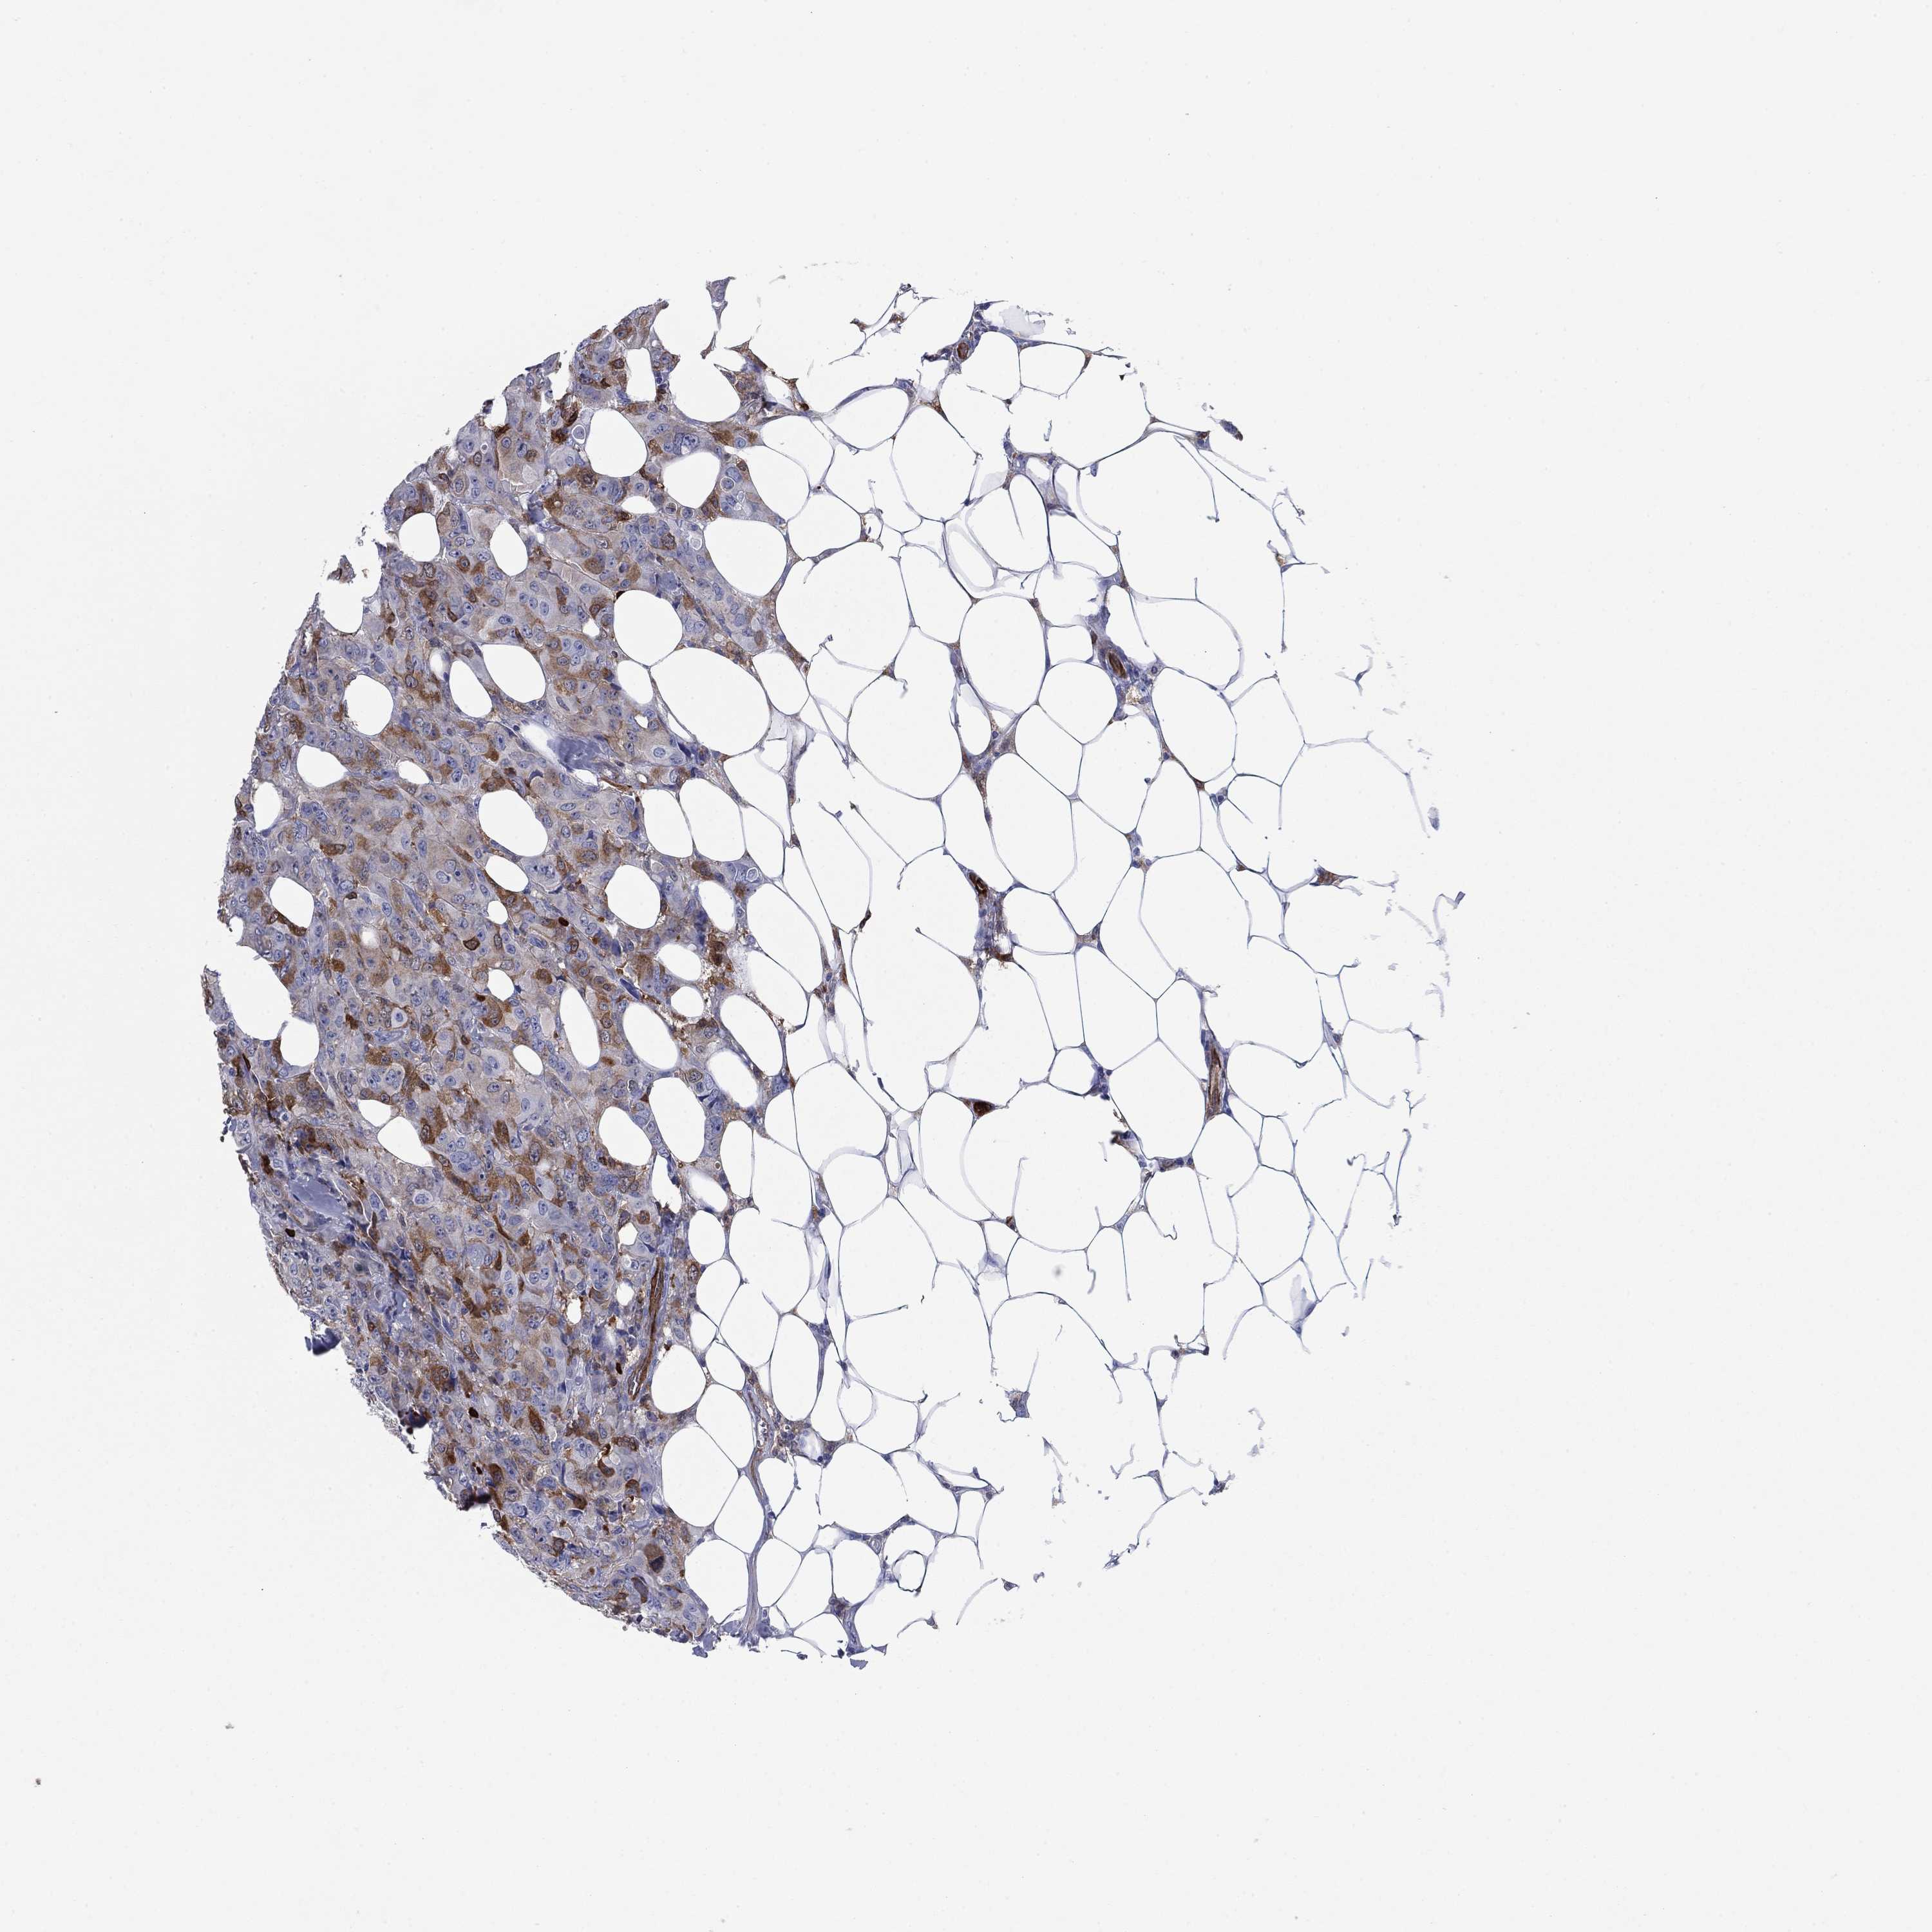

BRCA TCGA BRCA VALIDATION PROTEIN EXPRESSION

ANTIBODIES

AND

VALIDATION